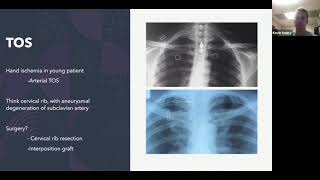

Guiding Light: An Animated Journey through Endovenous Thermal Ablation Vascular ABSITE Review

Vascular ABSITE Review ESPAL : Endoscopic Sphenopalatine Artery Ligation / Cautery